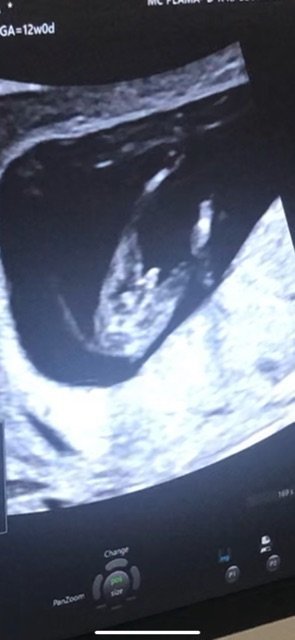

Днес бях на преглед, понеже не се чувствам добре и си взех болничен вече.

В 12 г.с съм и днес доктора направи “предположение” за пола🤔

Излезе, че с 5 дни съм напред.